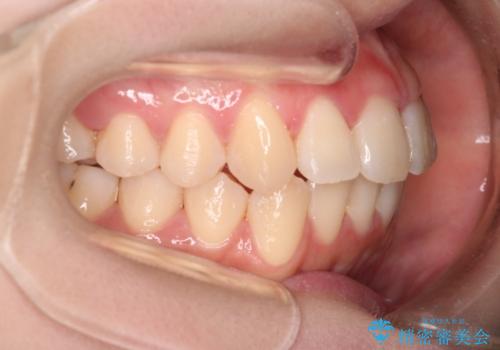

【インビザライン】マウスピースで開咬改善

- 開咬を主訴に来院されました。

IPR(歯と歯の間を削る処置)と顎間ゴムを行いながら、インビザラインで開咬を治療する計画を立てました。

治療をしながら、MFT(口腔筋機能療法)も行っていくことにしました。

歯の移動量が多いケースでしたが、患者様にマウスピースの使用とゴム掛けを頑張っていただいたので

リファイメント1回のみで治療を終わることができました。